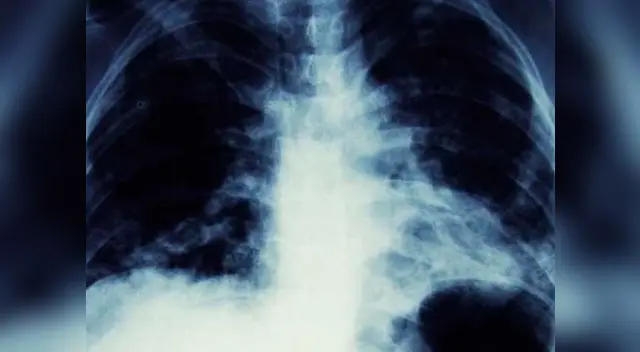

Las radiografías de tórax, mostraban una terrible mancha negra en su pulmón izquierdo, lo que era interpretado como un posible cáncer; sin embargo, además de la tos, no había más signos que indicaran que en realidad se trataba de esta terrible enfermedad.

Resulta que la mancha negra se trataba de un pequeño cono de tráfico de 'Playmobil' que le habían regalado en su cumpleaños número 7.

Los médicos sorprendidos no podían creer que el objeto hubiera vivido en su interior durante 40 años: “Finalmente encontró su cono perdido de Playmobil en el último sitio en el que se le hubiese ocurrido mirar”, decía el informe médico.